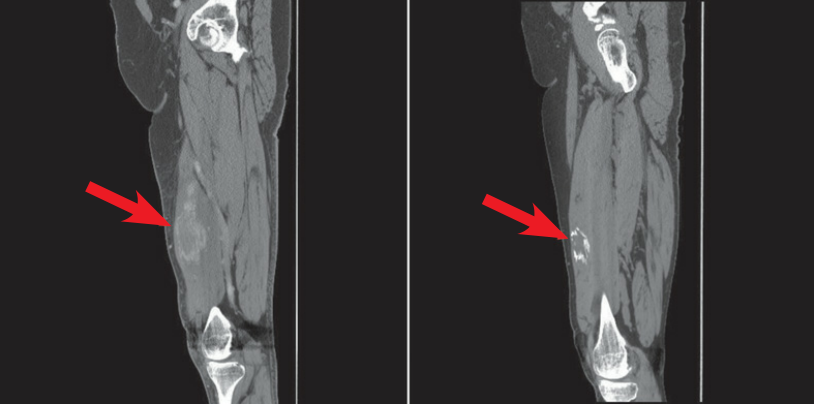

左图:X 线显示线状钙化影 (左蓝色箭头)。右图:随访 4 个月,可见钙化增多 (红色箭头),符合异位骨化。